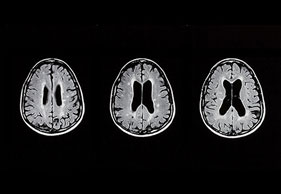

• MRT-Kopf (Erweiterung der Vorderhörner, Atrophie Straitum)